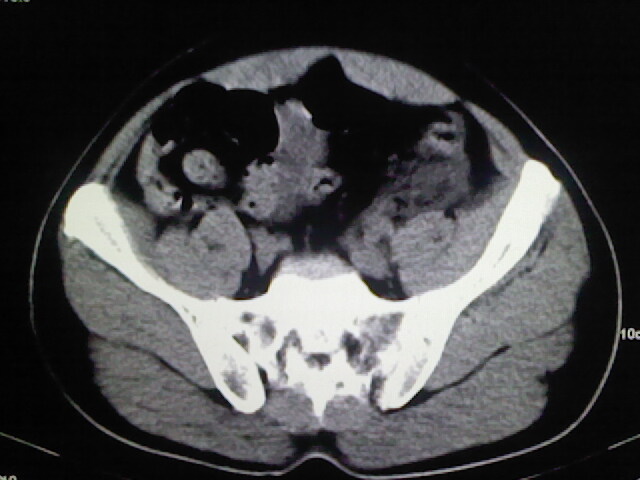

以下是引用zsl6918在2009-2-7 7:29:00的发言:[br]请提供介入的方式方法,肾及输尿管改变考虑与介入损伤有关,漏了,尿液外渗。

以下是引用余辉在2009-2-7 8:27:00的发言:[br]可能是硬化剂烧穿囊壁进入肾盂输尿管了,尿漏。不除外介入或碎石术后合并感染[br]患者术后怀疑结石,接着就碎石了?就怀疑没有确诊吗?碎石用的什么方法?气压弹道还是体外超声?如果这样的话责任人都难找

以下是引用随光逐影在2009-2-7 8:46:00的发言:[br]支持3楼意见。[br]另:不排除左肾及肾周感染可能。